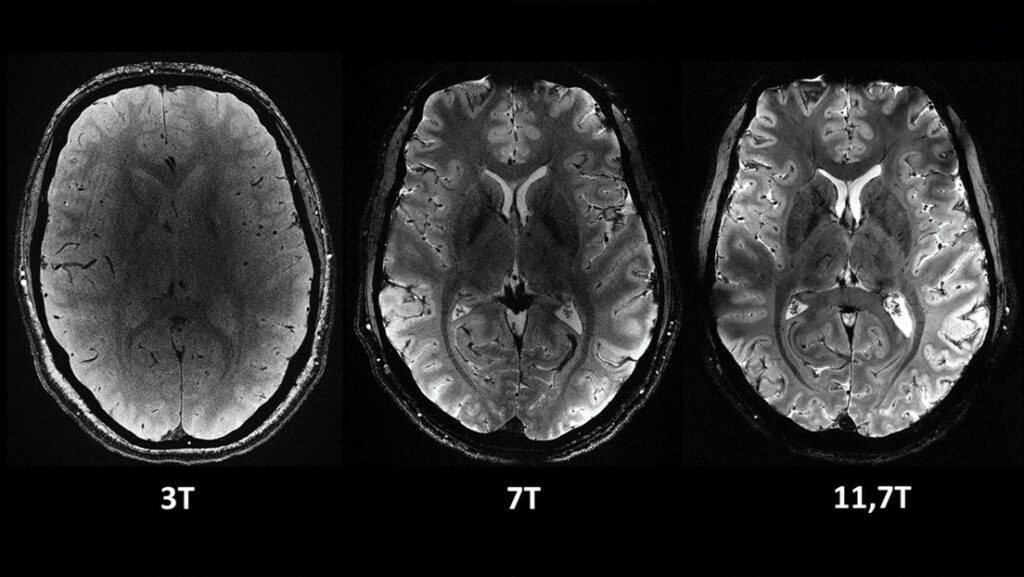

Las más notables imágenes anatómicas del cerebro nunca antes obtenidas se tomaron en apenas cuatro minutos. Los expertos señalan que su resolución es impresionante para un lapso temporal de adquisición tan corto. Se logró una resolución en el plano de 0,2 mm y grosor de corte de 1 mm, lo que representa un volumen equivalente a unos pocos miles de neuronas.

En comparación, la misma calidad de imagen requeriría horas con los escáneres de resonancia magnética actualmente disponibles (de 1,5 o 3 teslas). Esto no es realista en la práctica, ya que los pacientes no se sentirían cómodos y cualquier movimiento haría que la imagen se vea “borrosa”.